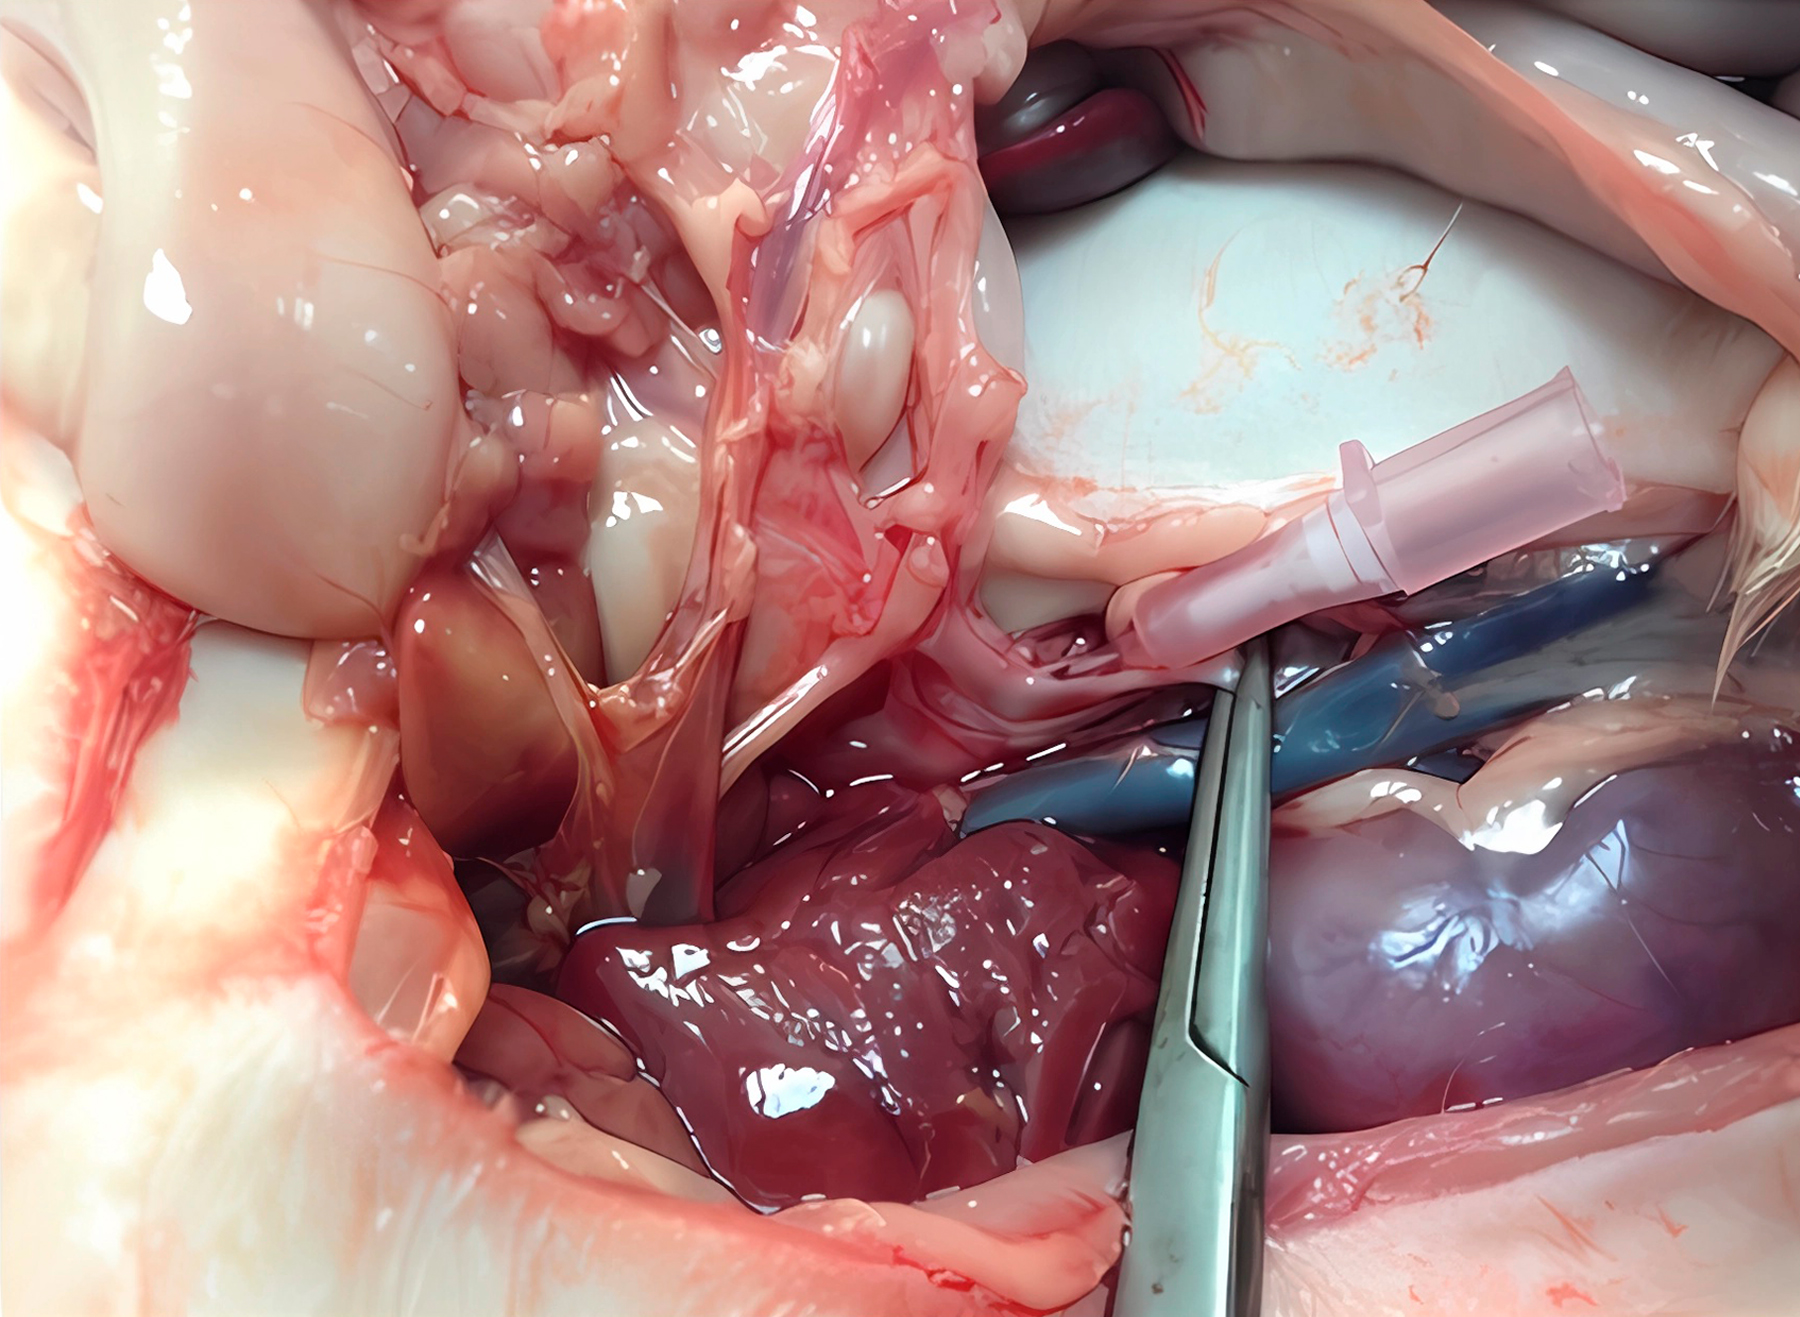

Resolución y Evolución:

Corrección quirúrgica exitosa de la anomalía vascular. Recuperación favorable del paciente con normalización del cuadro clínico.